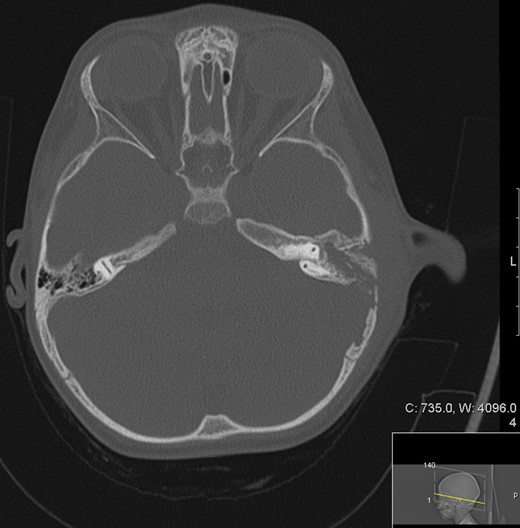

Otogenic TB was first described by Jean Loius Petit [4]. Records from the early 20th century report an incidence of TB otitis media of 2.8% in the paediatric population by Fraser et al. (1915) [4]. The landscape has changed immensely since this time in line with the general reduction in TB associated with immunization programmes and socioeconomic factors such as improved housing [1]. Most sources are now associated with overseas contacts but even in TB endemic countries the occurrence of paediatric otogenic TB is rare with only a few paediatric case reports presented in literature (Fig. 4). Intracranial complications of otomastoiditis is even rarer and include meningitis, encephalitis, empyema, extradural collections and sinus venous thrombosis [5], which makes the management of such cases extremely challenging. And out of paediatric case reports presented, only one was found to have reported intracranial complications [6].

Literature overview of paediatric otomastoiditis case reports from 1980 onwards searched through OVID Medline and Embase databases and references of searched case reports. (With exclusion of non-English language-based case reports.)